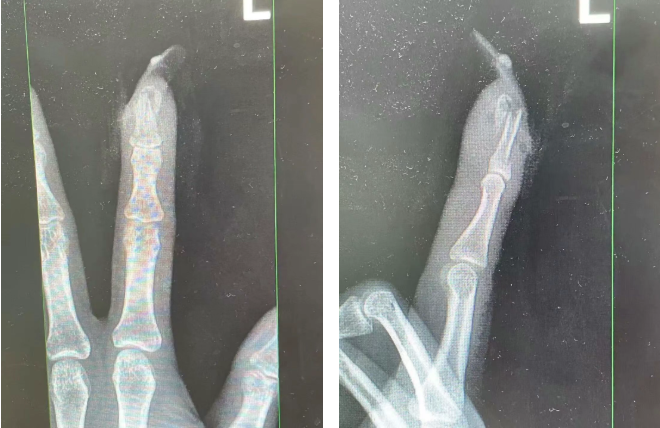

经检查

王女士指甲断裂

部分甲床外露

医生表示如果没有美甲

伤害不会这么严重

王女士受伤手指的X光影像。图源:杭州市临平区中西医结合医院